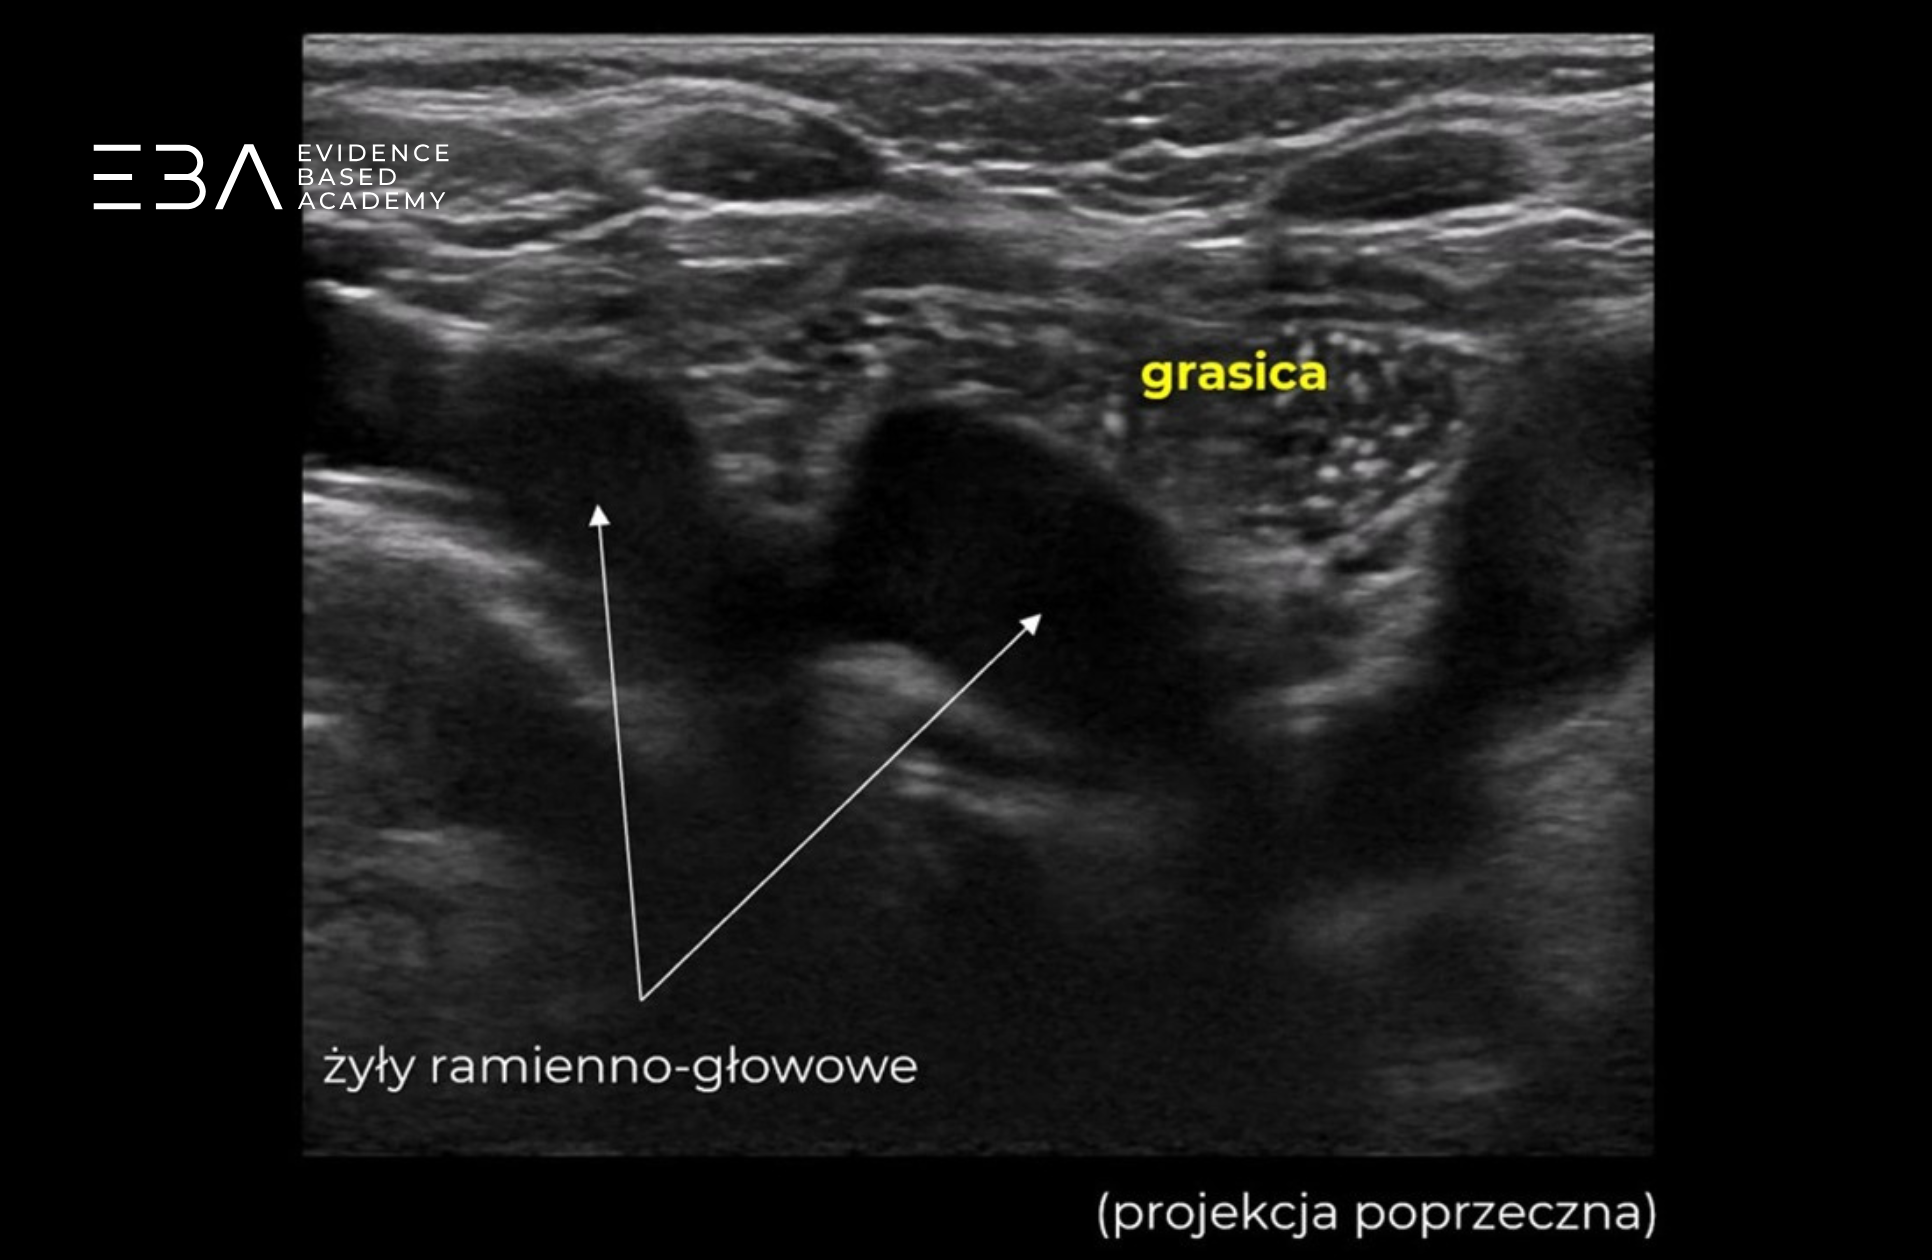

Grasica w skanie poprzecznym z podpisami żył ramienno-głowowych.